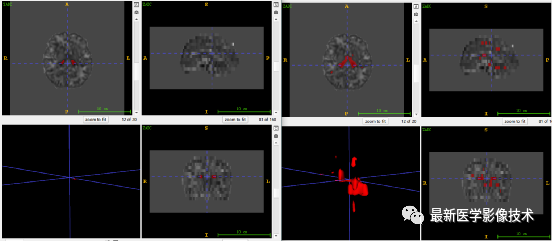

6、测试集分割结果

左图是金标准结果,右图是预测结果。